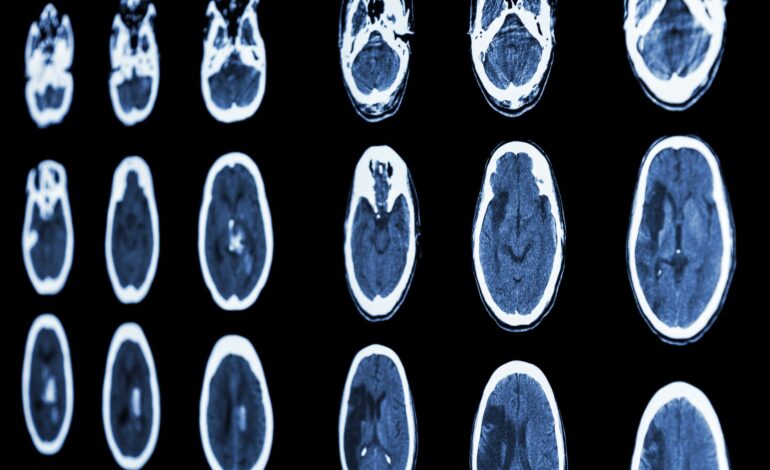

Les équipes médicales de l’hôpital régional de Tozeur ont réussi à traiter un cas de AVC chez une patiente âgée de 65 ans en utilisant la télémédecine, selon un communiqué publié ce lundi par le ministère de la Santé.